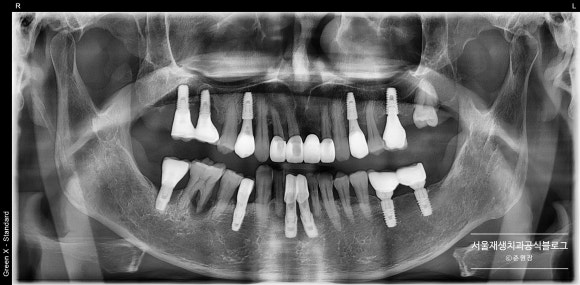

임플란트 주위의 불편감을 호소하시는 환자분의 엑스레이입니다.

어디에 어떤 문제가 있었을까요?

두 개의 노란 동그라미 중 상방에 있는 것을 먼저 보실까요?

임플란트 2개를 둘러싼 치조골(=잇몸뼈)가 완전히 녹아내렸습니다.

사실은 끝에서 두번째 임플란트의 심한 골소실에 집중하고 있었는데,

막상 구강 내에서 검사를 하니

맨 끝 임플란트 또한 심하게 흔들리고 있다는 것을 알게되었습니다.

아래의 동그라미 속에는

마찬가지로 치조골(=잇몸뼈)가 절반 이상 흡수된 자연치아가 관찰됩니다.